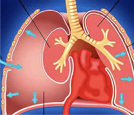

Η υπεζωκοτική κοιλότητα είναι ο χώρος ανάμεσα στα δυο πέταλα του υπεζωκότα που επικαλύπτουν και περιβάλουν τους πνεύμονες.

Η παρουσία αέρα στην υπεζωκοτική κοιλότητα σημαίνει τρία πράγματα:

β). Επικοινωνία των κυψελίδων με την υπεζωκοτική κοιλότητα.